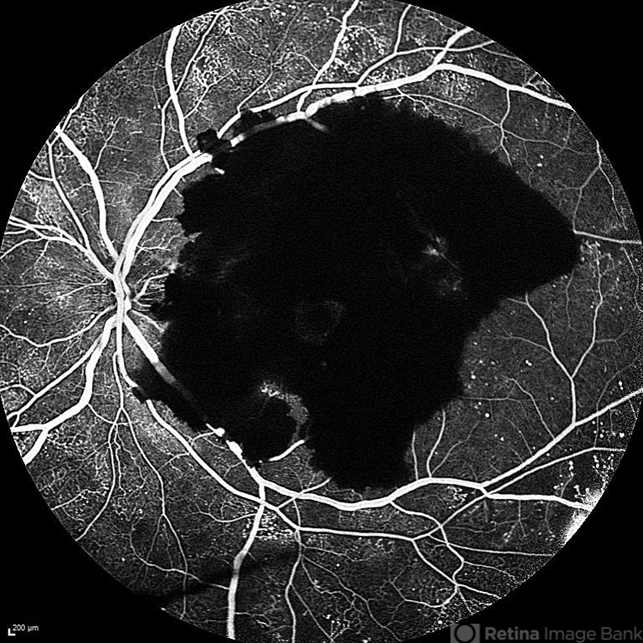

- Subhyaloid hemorrhage without foveal involvement in diabetic patient

- subhyaloid hemorrhage, fluorescein angiogram (FA)

- Subhyaloid hemorrhage without foveal involvement fluorescein angiography.